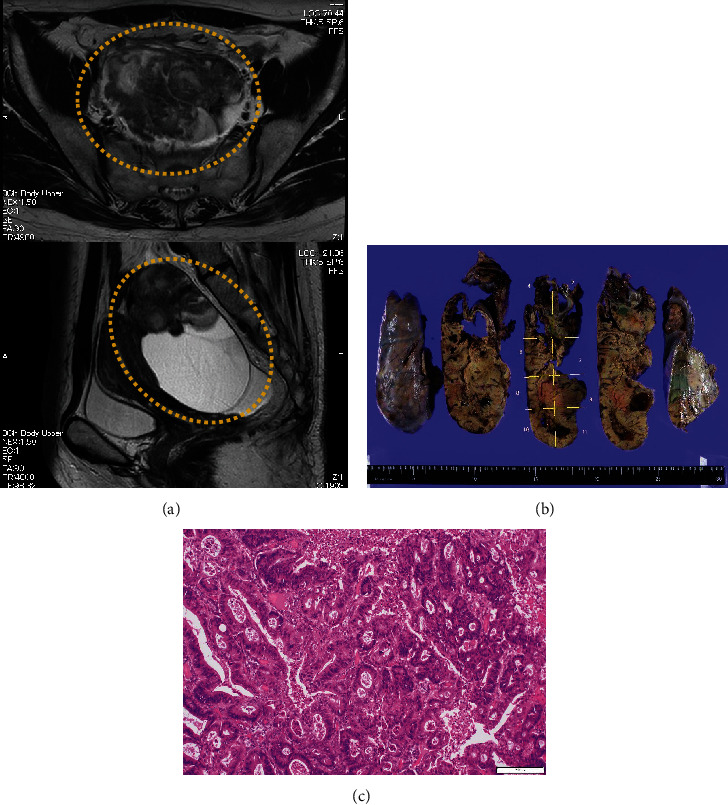

从生殖器外部位转移到子宫的情况非常罕见。我们介绍了一例女性病例,她曾接受过小肠癌手术,随后出现左侧卵巢和子宫转移。一名 50 多岁的无子宫妇女因患小肠癌接受了腹腔镜小肠部分切除术和淋巴结清扫术。五个月后,计算机断层扫描(CT)发现左侧卵巢肿瘤和腹水。她接受了双侧附件切除术和辅助化疗,卵巢肿瘤被诊断为小肠癌转移。小肠癌手术两年后,正电子发射断层扫描(PET)-CT 扫描发现子宫积液。宫颈细胞学检查未发现上皮内病变或恶性肿瘤。子宫内膜组织学检查显示为子宫腺癌。患者接受了全腹子宫切除术,随后接受了辅助化疗。子宫肿瘤的组织病理学和免疫组化结果显示,这是一种小肠癌转移瘤(细胞角蛋白7 [CK7] [-]、细胞角蛋白20 [CK20] [+]、特殊AT-富序列结合蛋白2 [SATB2] [+]、配对盒基因2 [PAX2] [-]和雌激素受体[ER] [-])。对于癌症患者来说,组织病理学和免疫组化对于区分原发性和转移性肿瘤以及指导治疗方案的选择非常重要。

Uterine metastases from extragenital sites are rare. We present a case of a woman who had undergone surgery for small intestinal cancer and subsequently developed metastases in her left ovary and uterus. A nulliparous woman in her 50s underwent laparoscopic partial small bowel resection with lymph node dissection for small intestinal cancer. Five months later, computed tomography (CT) revealed a left ovarian tumor and ascites. She underwent bilateral adnexectomy and adjuvant chemotherapy, and the ovarian tumor was diagnosed as a small intestinal cancer metastasis. Two years after the small intestinal cancer surgery, a positron emission tomography (PET)-CT scan revealed a uterine accumulation. Cervical cytology was negative for intraepithelial lesion or malignancy. Endometrial histology showed an adenocarcinoma of the uterus. The patient underwent total abdominal hysterectomy followed by adjuvant chemotherapy. Histopathology and immunohistochemistry of the uterine tumor revealed that it was a metastasis of small intestinal cancer (Cytokeratin 7 [CK7] [-], Cytokeratin 20 [CK20] [+], Special AT-Rich Sequence-Binding Protein 2 [SATB2] [+], Paired Box Gene 2 [PAX2] [-], and estrogen receptor [ER] [-]). In patients with cancer, histopathology and immunohistochemistry are important for distinguishing between primary and metastatic tumors and for guiding the choice of treatment.